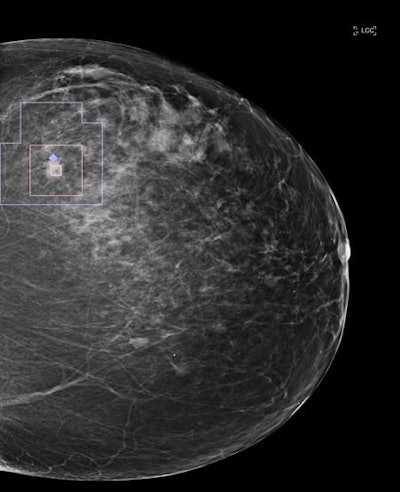

After testing a number of image enhancement methods, the Zebra team found it could optimize the representation of mammographic features for deep learning by applying "false color" to mammography images that had been processed with CLAHE. Areas of black and white density are converted on an image into a spectrum of color on the red, green, and blue (RGB) scale.

Next, these processed images are input into two independent CNN algorithms: One CNN focuses on a lower-resolution image of the whole breast, while the second receives smaller patches of the same image. Both CNNs were based on the Google Inception V3 model and were pretrained on data from the ImageNet database. Training and testing were performed on datasets of mammography images from the Digital Database for Screening Mammography and the proprietary Zebra Mammography Dataset of 1,739 full-sized mammograms.

"This approach is intuitively aligned with how radiologists assess mammograms: first globally and then 'zooming in' to analyze discrete regions," the authors wrote. "Indeed, some features of malignancy, such as regional architectural distortion or asymmetry are best revealed on the image level; whereas others, such as microcalcifications or masses, are best seen in magnification."